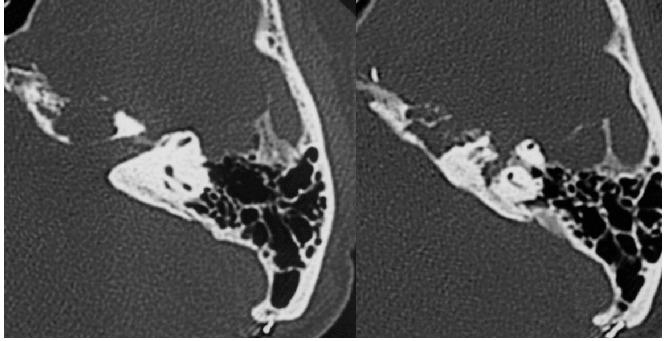

Facial nerve schwannomas involving posterior and middle fossas are quite rare. Here, we report an unusual case of cerebellopontine angle facial schwannoma that involved the middle cranial fossa, two years after the first operation. A 53-year-old woman presented with a 3-year history of a progressive left side hearing loss and 6-month history of a left facial spasm and palsy. Magnetic resonance imaging (MRI) revealed 4.5 cm diameter of left cerebellopontine angle and small middle fossa tumor. The tumor was subtotally removed via a suboccipital retrosigmoid approach. The tumor relapsed towards middle cranial fossa within a two-year period. By subtemporal approach with zygomatic arch osteotomy, the tumor was subtotally removed except that in the petrous bone involving the facial nerve. In both surgical procedures, intraoperative monitoring identified the facial nerve, resulting in preserved facial function. The tumor in the present case arose from broad segment of facial nerve encompassing cerebellopontine angle, meatus, geniculate/labyrinthine and possibly great petrosal nerve, in view of variable symptoms. Preservation of anatomic continuity of the facial nerve should be attempted, and the staged operation via retrosigmoid and middle fossa approaches using intraoperative facial monitoring, may result in preservation of the facial nerve.

累及后颅窝和中颅窝的面神经鞘瘤相当罕见。在此,我们报告一例不寻常的桥小脑角面神经鞘瘤病例,该肿瘤在首次手术后两年累及中颅窝。一名53岁女性,有3年进行性左耳听力减退病史及6个月左侧面部痉挛和面瘫病史。磁共振成像(MRI)显示左侧桥小脑角有直径4.5 cm的肿瘤及中颅窝小肿瘤。通过枕下乙状窦后入路将肿瘤次全切除。肿瘤在两年内复发并向中颅窝发展。通过颞下经颧弓截骨入路,除累及面神经的岩骨部分肿瘤外,其余肿瘤被次全切除。在这两次手术过程中,术中监测均识别出面神经,从而保留了面部功能。鉴于症状多样,本例肿瘤起源于面神经的广泛节段,包括桥小脑角、内耳道、膝状神经节/迷路段,可能还包括岩大神经。应尝试保留面神经的解剖连续性,采用术中面神经监测的乙状窦后和中颅窝入路分期手术,可能有助于保留面神经。